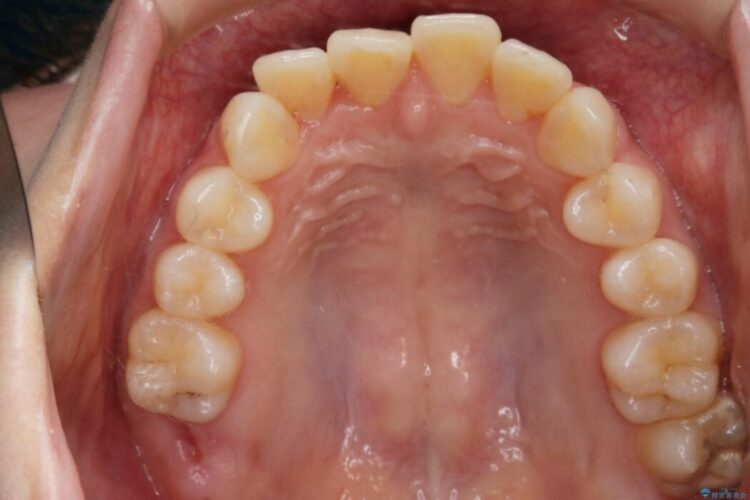

【20代女性】ブライダルに向けた矯正できれいなスマイルラインへ

笑った時に見える歯並びをきれいにしたいとの主訴で来院されました。

ガタつきの度合いから抜歯は不要と判断しましたので、マイクロインプラントを用いて歯全体を遠心移動させていくことでねじれや噛み合わせのズレを改善していく計画を立てました。